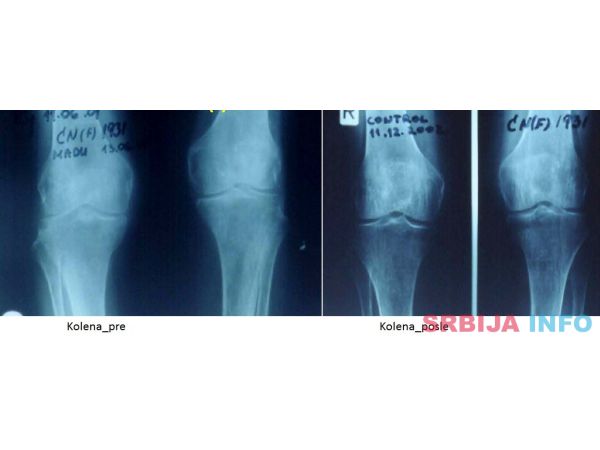

• posebno efikasno obnavljanje hrskavice – jedinstveno u svetu.

• degenerativnih koštano-zglobnih oboljenja i povreda (obnavljanje međuzglobnog prostora kičmenih pršljenova; obnavljanje zglobnog prostora kuka; obnavljanje zglobnog prostora kolena; zarastanje komplikovanog preloma pršljena; zarastanje preloma drugih kostiju; obnavljanje potpornog tkiva zubâ u slučajevima paradontopatije);